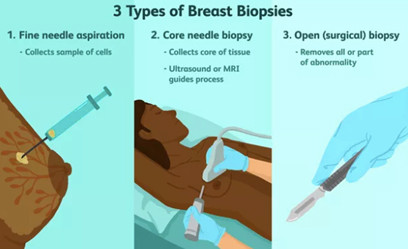

Sinh thiết

Khi phát hiện khối u hoặc vùng bất thường ở vú sau khi chụp hình ảnh, bác sĩ có thể cần trích xuất một lượng nhỏ mô để xét nghiệm bệnh lý.

Sinh thiết hỗ trợ hút chân không

Là phương pháp sử dụng kim sinh thiết chuyên dụng với cỡ kim từ 8G – 10G để cắt bỏ hoàn toàn các tổn thương lành tính có kích thước

Giải phẫu bệnh

Báo cáo bệnh lý được tạo ra sẽ nêu rõ các phát hiện và chẩn đoán cho từng mẫu được lấy. Thông tin này sẽ được gửi đến bác sĩ để quản lý việc chăm sóc và đưa ra kế hoạch điều trị.